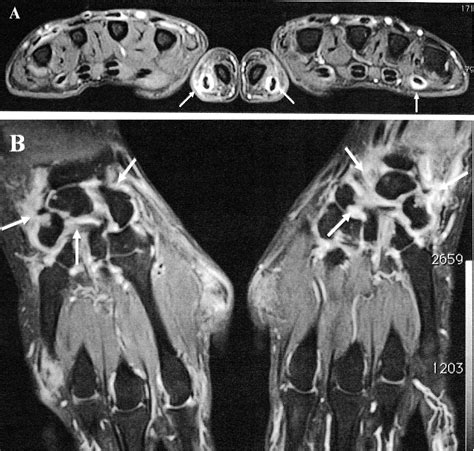

Interpreting the results of an MRI of hand requires the expertise of a radiologist. The images will be reviewed to identify any abnormalities or conditions. Here are some key points that the radiologist will look for:

• Bone Structures: The radiologist will examine the bones for any fractures, deformities, or signs of bone diseases.

• Soft Tissues: The condition of ligaments, tendons, and muscles will be assessed for tears, inflammation, or other injuries.

• Joints: The joints will be evaluated for signs of arthritis, inflammation, or other joint-related issues.

• Nerves: The nerves will be checked for compression or other abnormalities that could cause pain or numbness.

• Tumors and Cysts: Any masses or cysts within the hand will be identified and characterized.